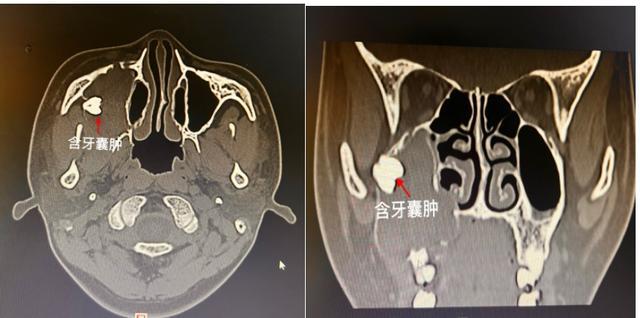

18岁的小强刚刚参加完高考,对未来的生活充满憧憬,可是最近三个月,右侧面颊部渐大的隆起让这个开朗的大男孩不禁开始了“颜值焦虑”。带着紧张的心情,家人陪同小强来到了湖南省第二人民医院(省脑科医院)耳鼻喉头颈外科就诊,门诊余丽亚副主任医师对患者进行了仔细的检查后,诊断为上颌窦含牙囊肿。(见图)

根据小强的检查结果(见图),右侧上颌窦已被囊肿及囊液填的满满当当,上颌窦原本坚实的骨质被囊肿压迫变薄甚至吸收。只剩下周围一层薄薄的皮质骨,在右侧上颌骨接近颧骨的位置,卡着一颗明晃晃的牙齿。综合分析后,余丽亚副主任医师建议患者尽快办理出院,行手术治疗。